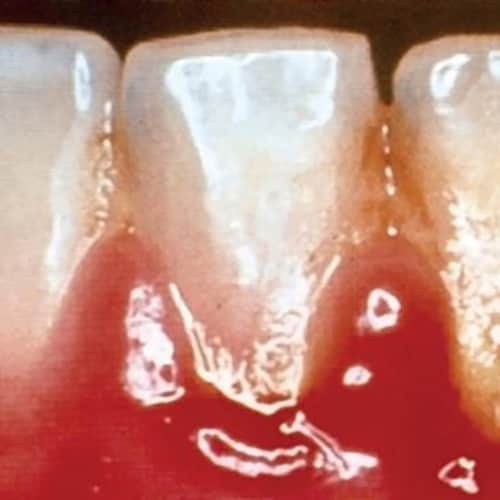

Localized Gingival Inflammation

Find images of localized gingival inflammation in patients at Colgate® Professional. We have more resources available for dentists and hygienists. -